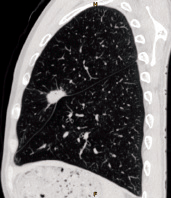

Tumor Detection

CT scan machines can spot abnormal growths (tumors) in organs like the lungs, liver, pancreas, and colon. For example, a low-dose CT scan is often used for lung cancer screening in high risk groups (e.g., long-term smokers), as it can detect small nodules that might be cancerous.